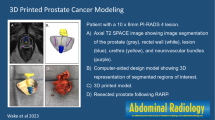

The ethical implementation of new technologies in surgery has been studied through the IDEAL guidelines [14], while the implementation of innovations into mainstream medicine can be described via their progress through the Gartner hype cycle [15]. 3D printing and robotic surgery currently occupy different stages on Gartner’s hype phase of technology. Due to its broad acceptance, uro-oncologic robotic surgery is currently ascending the ‘Slope of Enlightenment’. In comparison, despite widespread use in the field of engineering, 3D printing in surgery is a more recent application of the technology and has entered a stage of exponential growth [2] after an initial ‘Technology Trigger’. Contemporary medical innovation does not occur in a vacuum, with the intersection of new technologies becoming increasingly common (see Fig. 1).

A summary of included publications is contained within Table 1. Due to the sparsity of articles concerning the intersection of these two new technologies, all included studies are discussed below (see Fig. 3).

Patient education

The authors would like to acknowledge Professor Prokar Dasgupta for contribution of the image of an example 3D printed prostate model.